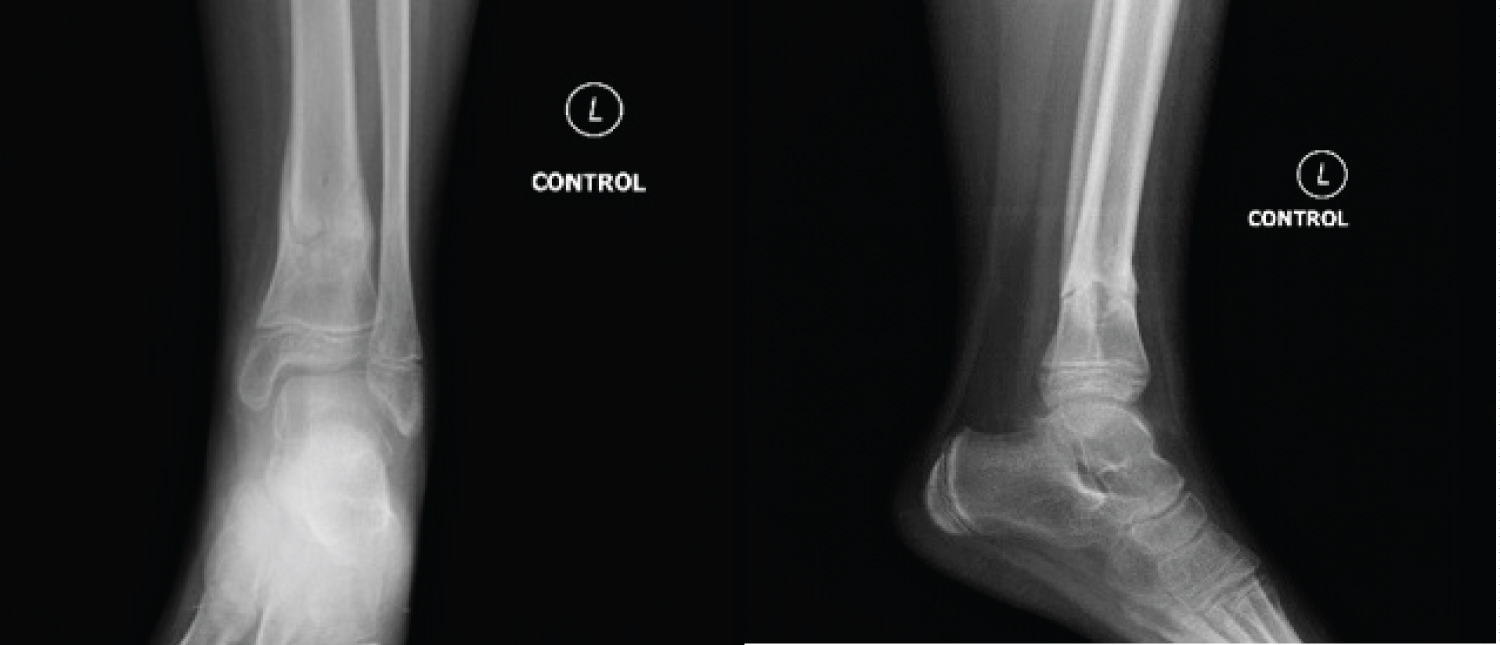

Two months after surgery, healing was marked on radiographs and the pins were consequently removed through a simple procedure (Figure 5). The patient was then examined. The range of motion in the operated side for both the ankle and the knee were evaluated with no difference compared to the non-operated side. Neither limb length dissimilarity nor malalignment were remarkable. No lameness was notable with full weight bearing. No surgery related complications were encountered during the past two months.

Figure 5: Two months after surgery radiographs showing evidence of fracture healing. View Figure 5

The patient was then seen and examined 15 months after surgery. The physical exam was absolutely normal with no eminent changes comparing to the last one. The radiographs have revealed total bone healing with respected length, rotation and alignment comparing to the other limb (Figure 6).

Figure 6: fifteen months after surgery radiographs showing total and anatomical healing. View Figure 6